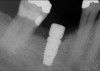

Fig 20. (Case 4) Radiograph of tooth No. 30, which had a hopeless prognosis.

Figure 20

Fig 21. Radiograph of extraction socket. Buccal plate was two-thirds resorbed.

Figure 21